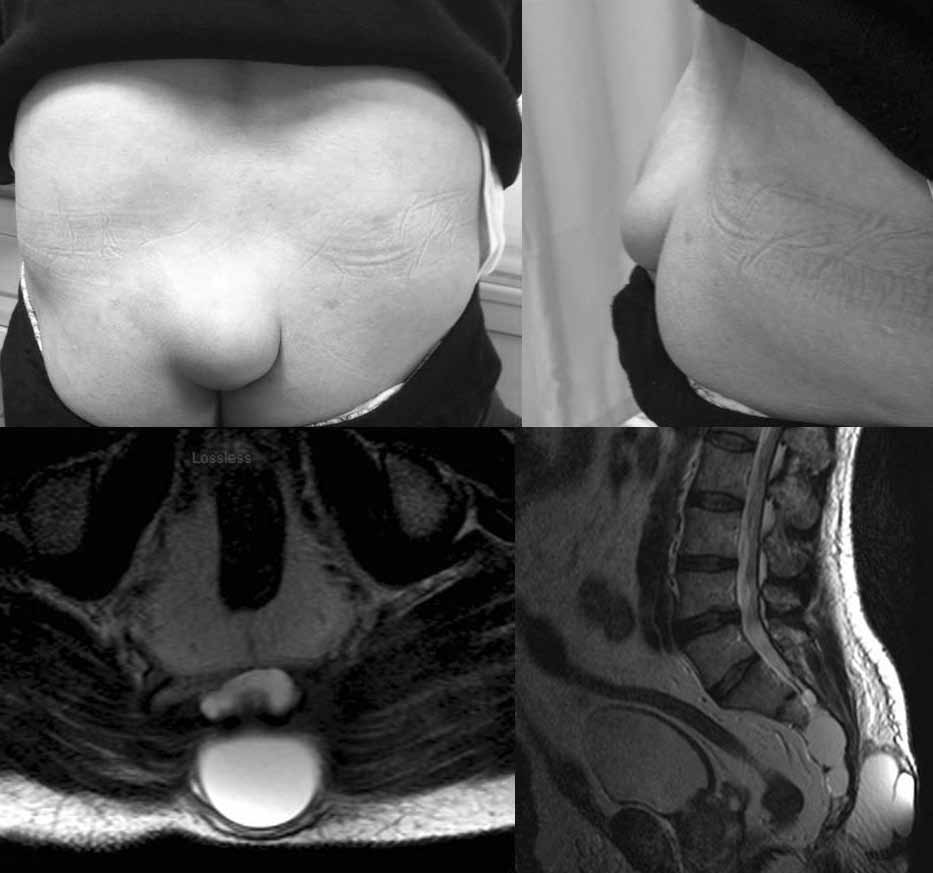

典型的“伪尾”

而“伪尾”,实则更接近于动物真正的尾巴,它是腰骶部区域的凸起物,病变实质可能为尾骨过长、脂肪瘤、畸胎瘤、软骨膜增生、胶质瘤及细长的寄生胎等。伪尾通常与潜在的严重病变相关。

“人尾”的形成原因复杂,可能与发育或非发育情况相关,如神经管闭合不全、脊柱裂、脊椎栓系综合征、脂肪瘤等。一项研究显示,腰骶部凸起物的成因主要包括:脂肪瘤(67%),畸胎瘤(25%)及脊膜膨出(4%)。为了确定治疗方法,进一步的影像学检查通常是必要的。